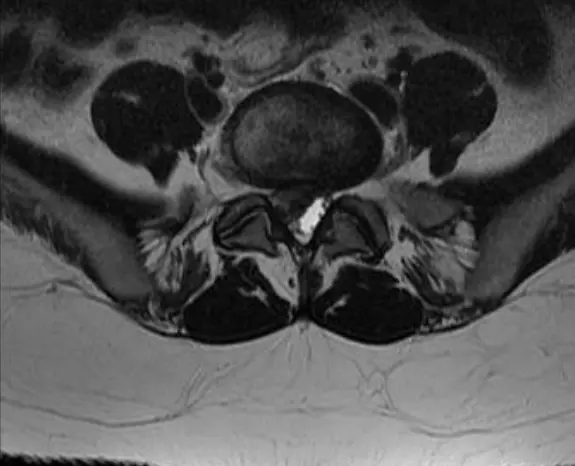

■ MRI (가장 정확한 검사)

추간판의 탈출을 확인할 수 있으며, cauda equina의 압박 소견도 확인할수 있음